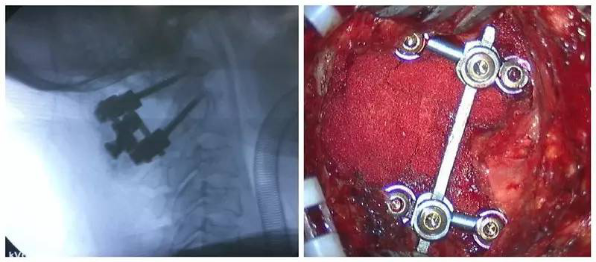

全麻后,显微镜下行颈后路减压+寰枢椎(C1~2)复位椎弓根螺钉钛棒内固定+植骨融合术。术中C臂下行C1~2复位椎弓根置钉。术后三个月复查见椎管减压后脊髓位置良好,寰枢椎脱位复位,局部可见骨融合。患者自述四肢麻木无力感明显好转。

7术中片子